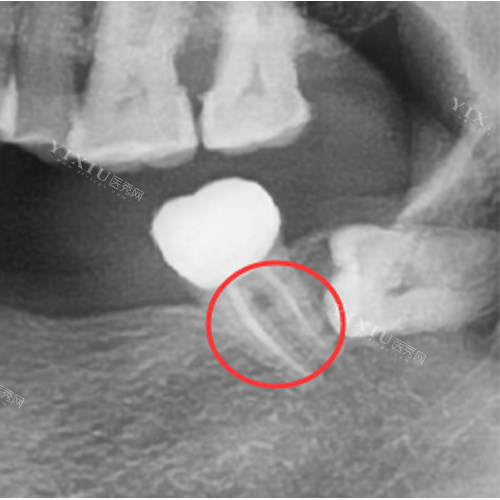

根管治疗:前牙800元起,后牙1200元起